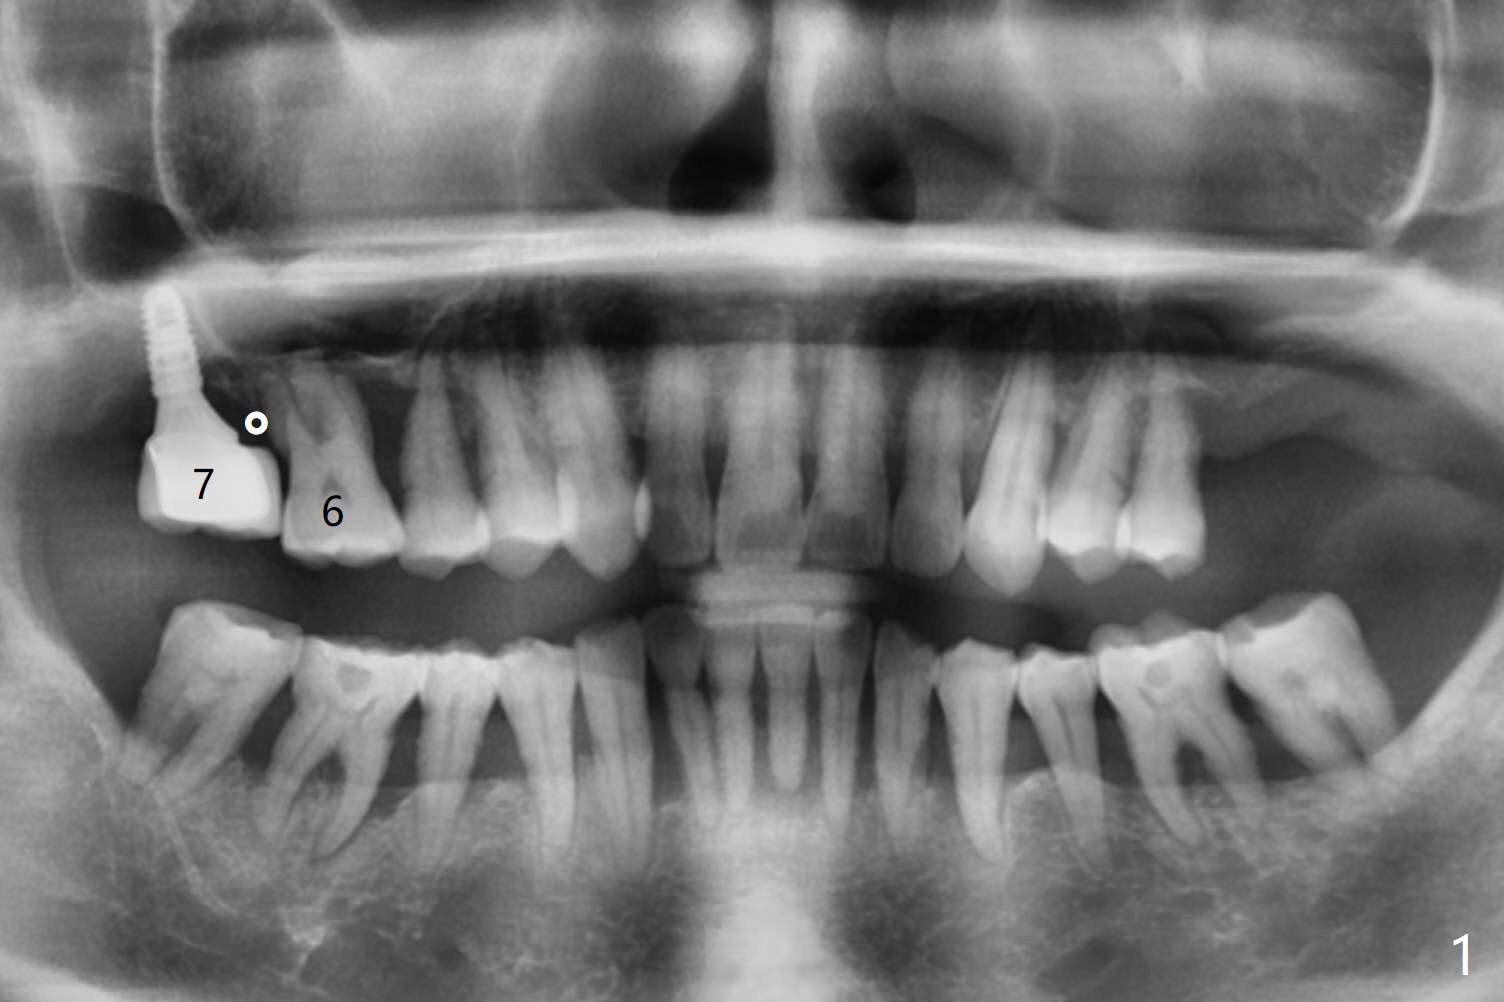

57岁女严重牙周炎,主诉右上磨牙食物堵塞(图一:圆圈)。第一磨牙骨质吸收,松动,需要拔除,尽管骨壁2-3毫米(图二),使用导航应该能取得5乘7.3毫米植体(图三绿色)初步稳定性。上颌窦膜厚,提升术不容易破裂,使用PRF膜预防及修补。由于近中骨质缺损严重(图三 *),植体可以再提高些(箭头),利用粘性骨做提升以及骨质缺损充填,似乎颊侧骨质多些(图五),植体可以小些,万一不行,就做提升和植骨。左上磨牙区骨壁更薄(图四,约1毫米),外提升术之后再种植。